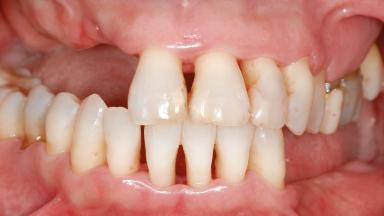

Shell Technique for Horizontal and Vertical Maxillary Bone Augmentation in a Partially Edentulous Patient with Aggressive Periodontal Disease

Prosthesis Type FDP

SAC Level Advanced

Defining Characteristics Up to three missing teeth to be replaced with an implant-borne restoration or restorations

Loading Protocol Conventional or early